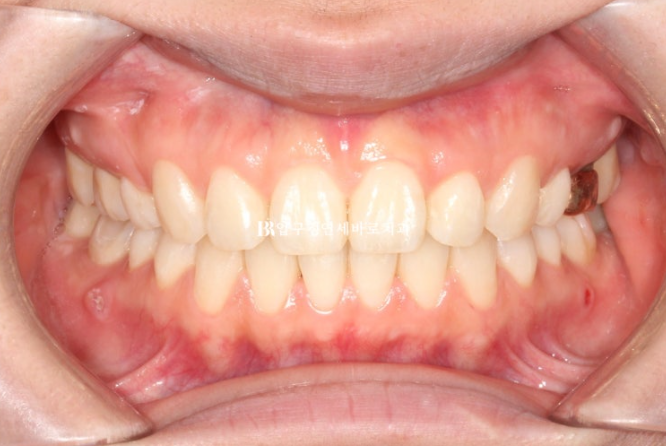

This patient came in June 2023 for protrusion and alignment improvement.

A mismatch in the midline is visible.

Because the upper front teeth protrude, the gap with the lower teeth is large.

If the front tooth bite is in this condition, the lips cannot close comfortably.

This can cause lip incompetence.

Because the front tooth protrusion was severe, the treatment plan was set as extraction orthodontics with removal of the two upper premolars, and treatment began.

At the initial examination, it was expected that if the lower lip were pulled back too much, the appearance would not be good, so for the lower arch the plan was to remove the impacted wisdom teeth without extracting the premolars, place mini-screws, and move the teeth back slightly.